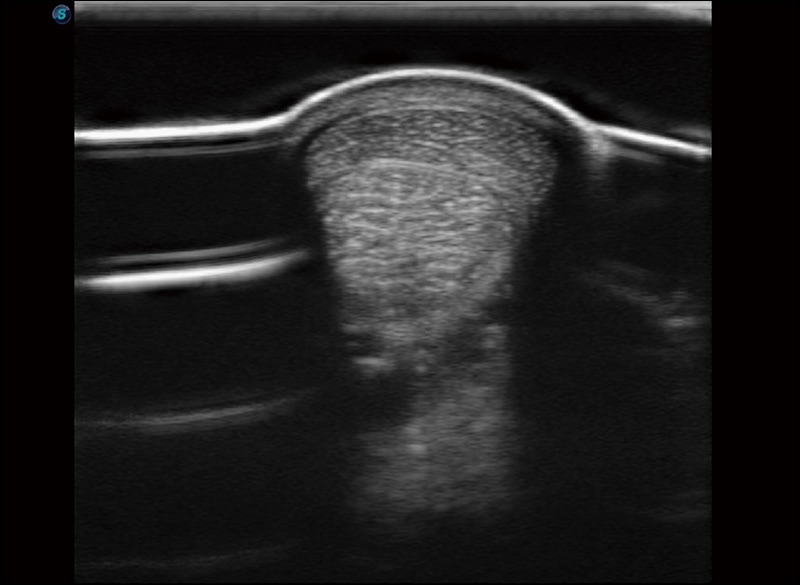

α1卓越的图像质量和便捷的工作流程,使每位宠物医生都能轻松扫查。其全面的兽用应用功能和紧凑型的结构设计,可以满足动物检查的多种需要。专业的预设检查模式和多领域测量软件包有助于为不同类型的动物提供检查, 让宠物医生能够出色的完成工作。

扩展成像

支持线阵和凸阵探头,一键操作即可获得更宽的图像视野

实时宽景成像

可实时观察感兴趣区域和病变位置